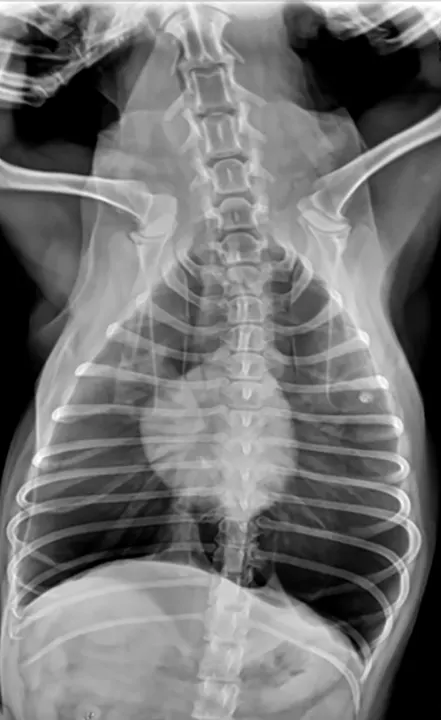

• Secure the pelvic limbs caudally in the same manner as the thoracic limbs, and place a sandbag across the neck to help with restraint. Ensure the patient is aligned laterally by putting one finger on the sternum and one on the dorsal spinous process and confirming they are equidistant to the table. If not, place a foam wedge under the patients lower side to acquire laterality, being sure to include a right or left marker. (See Figure 3.) Also, when critiquing the radiograph for laterality, make sure to check the rib heads for super-imposition. (See Figure 3A.)